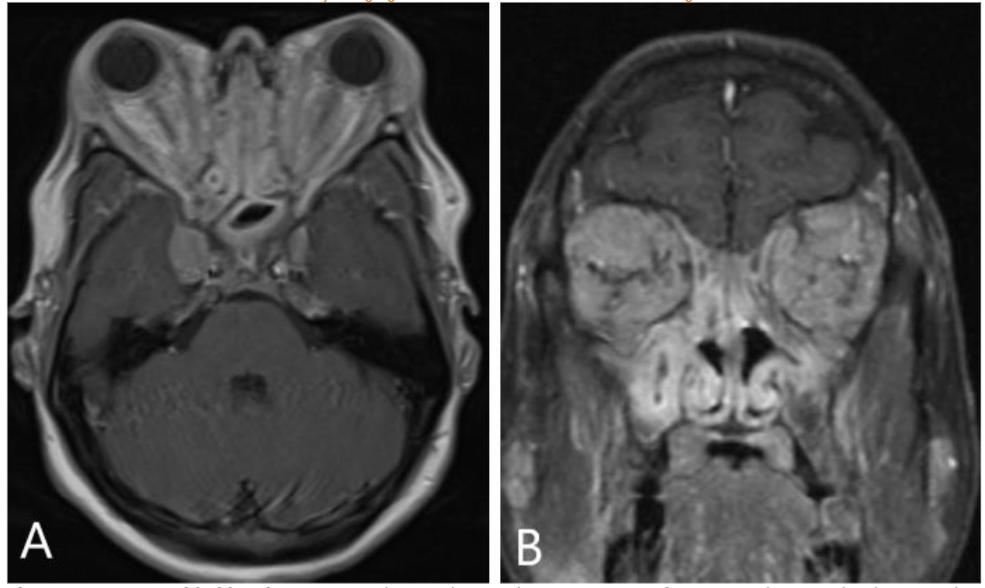

Orbital MRI provided a clearer characterization of diffuse retro-orbital soft tissue thickening, involving the fat, extraocular muscles, and lacrimal glands, leading to pronounced right orbital proptosis and globe eversion. The right globe was flattened with optic nerve stretching. The retrobulbar mass extended posteriorly into the orbital apex without cavernous sinus involvement, and there was also further extension into the lateral face, affecting the temporalis muscle.